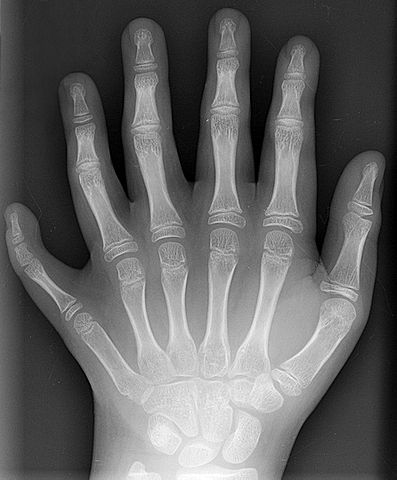

English: Conversion of a DICOM-format X-ray from a ten year old male showing polydactyly. This is the patient's left hand, posterior-anterior projection. Identifying tags and such have been stripped.

Deutsch: Röntgenaufnahme einer hexadaktylen linken Hand eines zehnjährigen männlichen Kindes. Allgemein bezeichnet die Polydaktylie das Vorhandensein zusätzlicher Finger oder Zehen, im häufigsten Fall von genau sechs Fingern oder Zehen wird die erbliche Anomalie konkret als Hexadaktylie bezeichnet.

Nederlands: Een Röntgenopname van een hexadactiele, d.i. zesvingerige, linker hand van een tienjarige jongen. Poly-, veel en hexa-, zes (van oud Grieks): bij deze erfelijke anomalie gaat het meestal om één extra vinger of teen.